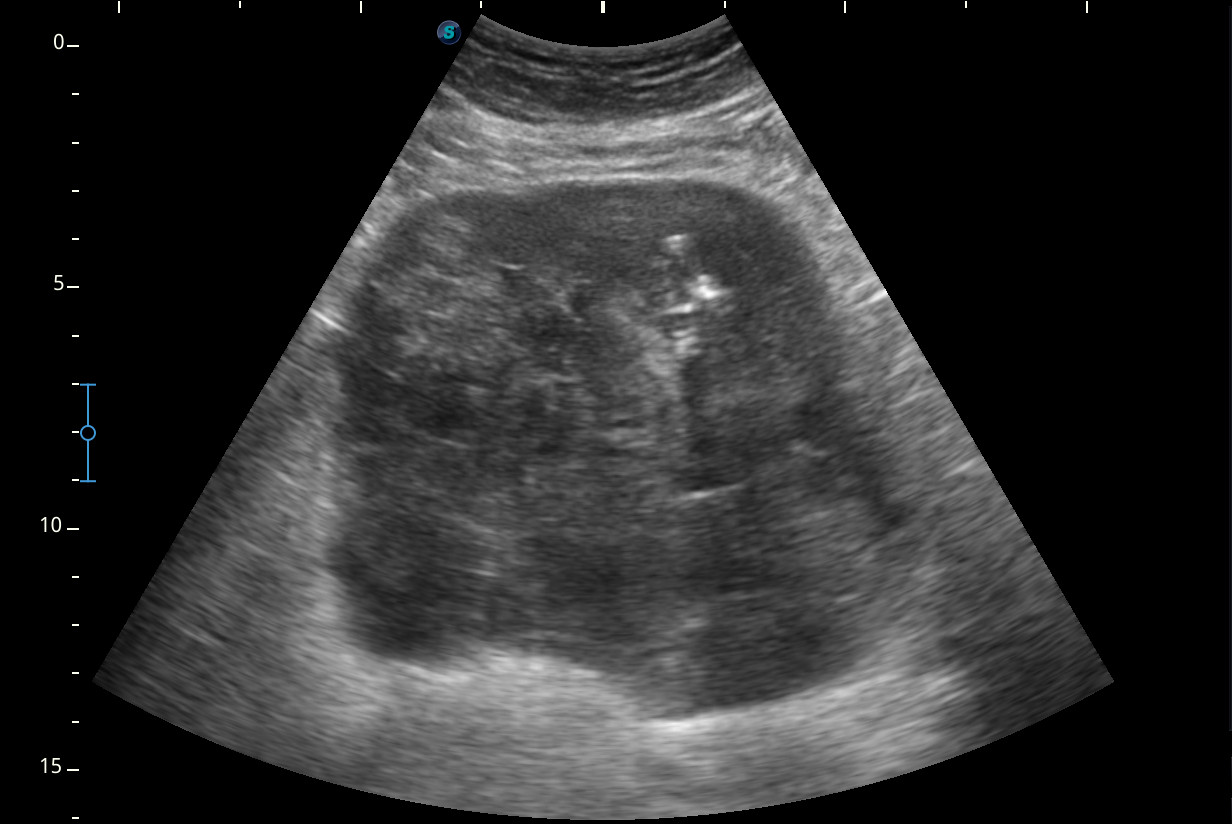

Hallazgos ecográficos

Se visualiza una masa heterogénea de unos 10 x 13 cm aproximadamente de diámetro con posibles focos necróticos y captación Doppler color, de dudosa organodependencia, que podría corresponder a un sarcoma retroperitoneal.